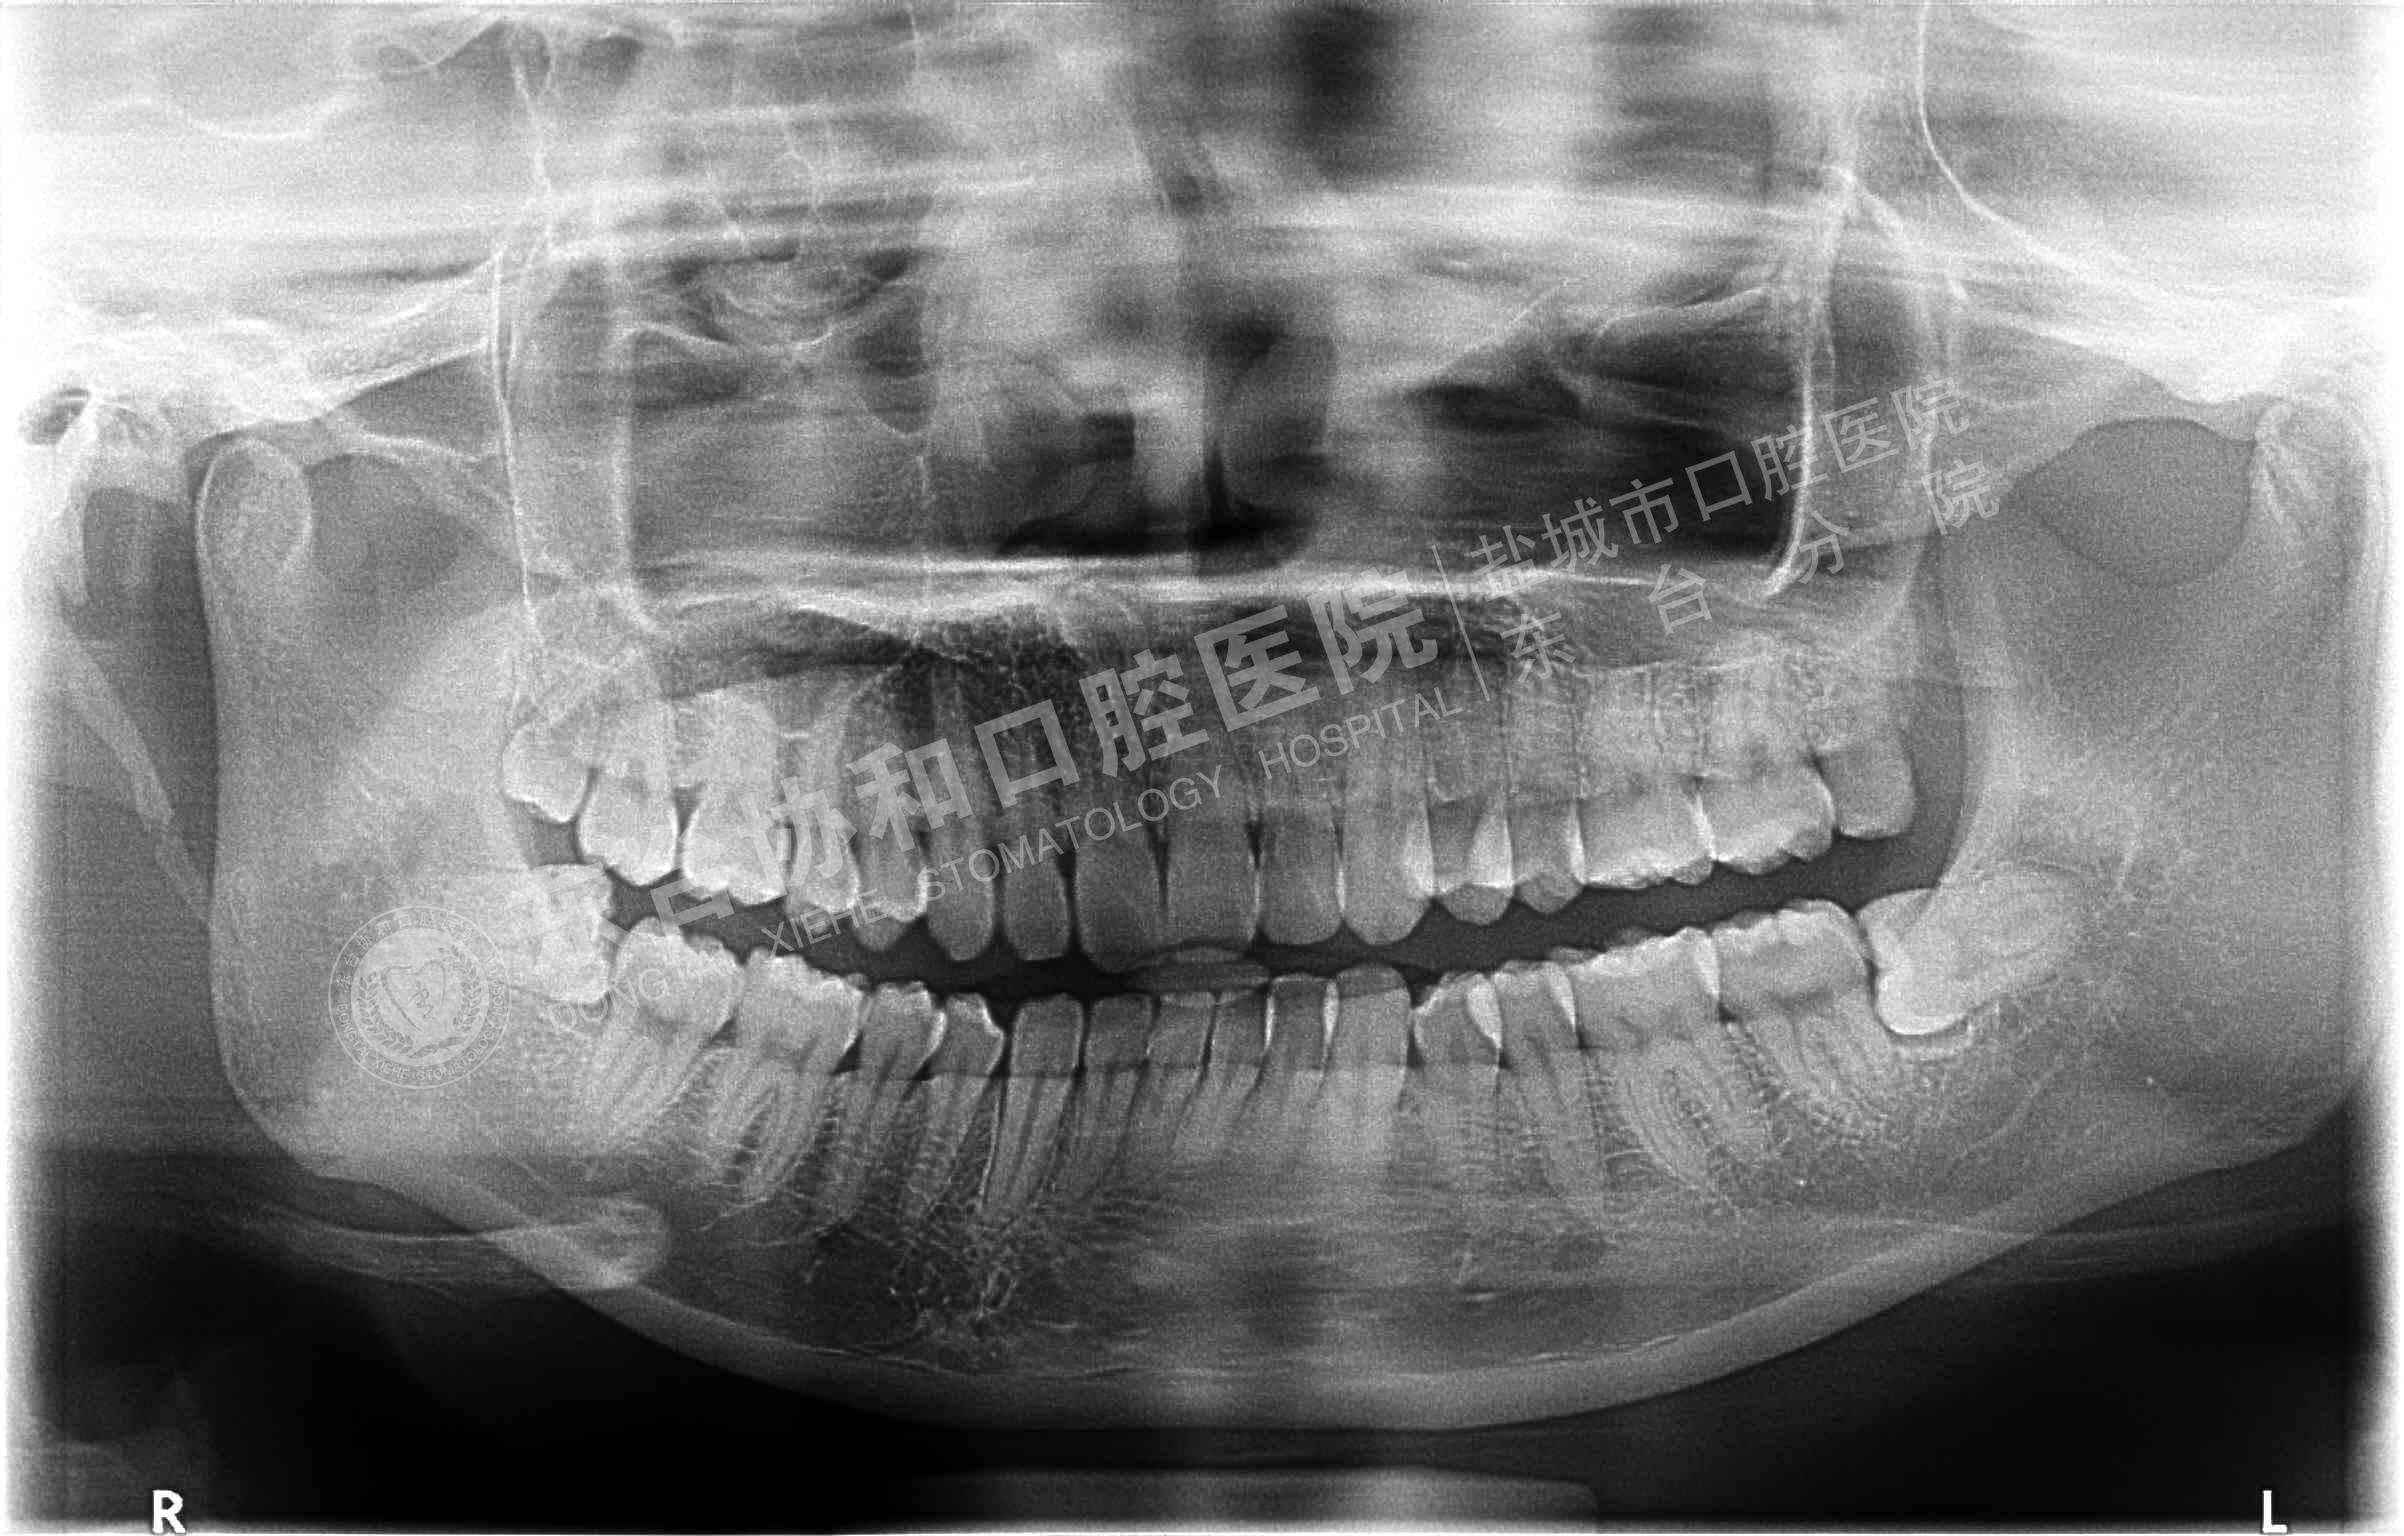

很多患者都很排斥拍牙片,認(rèn)為醫(yī)院是為了多收錢(qián)才讓他們拍的,其實(shí)這是一個(gè)錯(cuò)誤的想法,拍牙片是口腔科常用重要的檢查手段,臨床檢查只能直觀判斷牙冠和牙齦部分的情況,而對(duì)于牙根,牙槽骨、牙周膜等情況則必須通過(guò)牙片檢查。牙齒在牙片上顯示出白色阻射影像,其中牙釉質(zhì)阻射強(qiáng),牙本質(zhì)和牙骨質(zhì)阻射低于牙釉質(zhì),牙髓腔呈灰黑色影像,根管口至根尖孔呈逐漸變細(xì)的影像。

通過(guò)牙片除了了解牙齒的病變情況,還可以了解牙槽骨內(nèi)是否有埋伏牙、多生牙、牙源性腫瘤和囊腫等,依據(jù)牙片綜合分析可以提高牙齒診斷調(diào)節(jié)的準(zhǔn)確性和。

不同病種拍牙片的意義1、頜面部外傷:了解牙齒是否折裂、牙槽骨骨折程度和范圍。

2、牙齒硬組織病變:牙頸部牙根部齲齒、鄰面齲、確定齲壞的程度和齲壞的范圍;齲壞深度與牙髓腔的關(guān)系;了解齲壞與牙髓腔的距離;了解髓腔的變化情況和根尖周情況。

3、牙髓病變:牙片幫助檢查牙髓是否被吸收。

4、根尖周炎癥:了解病牙根管情況:如根管數(shù)目、粗細(xì)、彎曲度以及有無(wú)鈣化、有無(wú)內(nèi)吸收等情況;根管調(diào)節(jié)后的充填情況。如果牙齒需要做根管調(diào)節(jié),則牙片需要拍三張以上。調(diào)節(jié)前拍片是用來(lái)判斷是否根尖炎或者是囊腫的大小、范圍等,判斷是否需要根管調(diào)節(jié);根管預(yù)備術(shù)中片,檢查根管調(diào)節(jié)的長(zhǎng)度,調(diào)節(jié)后評(píng)價(jià)根管調(diào)節(jié)成功與否。

5、牙周炎癥:顯示牙槽骨吸收范圍和破壞程度。

6、用于阻生牙、埋伏牙及替換牙的檢查和調(diào)節(jié)。

7、牙片來(lái)確定乳牙和恒牙的相對(duì)位置,用來(lái)幫助醫(yī)生診斷乳牙是否能自行脫落還是需要拔除。

8、牙齒矯正:拍攝口腔全景片和頭顱側(cè)位片,以檢查骨骼和牙齒的發(fā)育情況。

9、拔牙檢查牙根情況以及牙槽骨破壞程度,牙齒是否拔除干凈以及牙槽窩形態(tài)是否完好。

10、種植牙拍牙片顯示牙槽骨的健康狀況、高度、密度,是否適合于種植牙;種植體的成活情況。